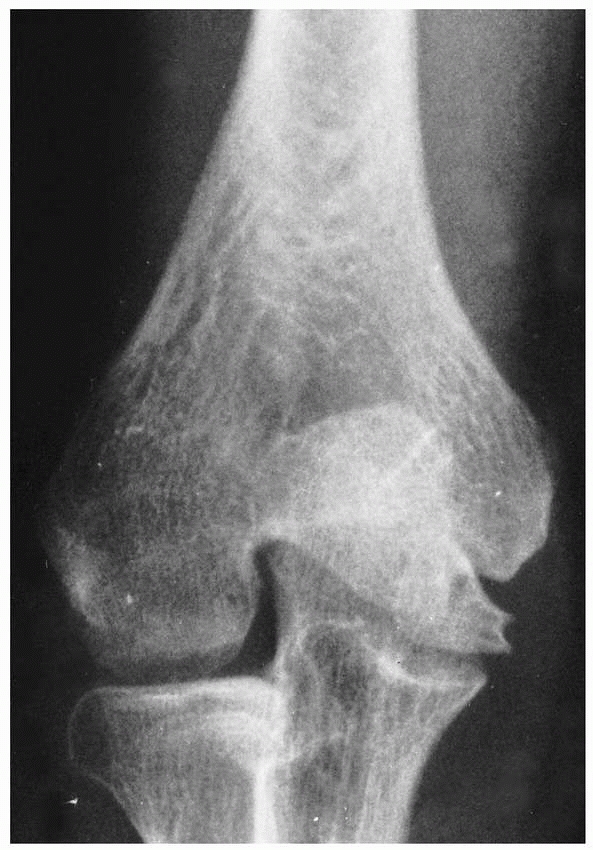

![]() |

FIGURE 15-13 Osteonecrosis of the lateral condyle after lateral condylar fracture in a 10-year-old boy. AP (A) and lateral (B) radiographs.

FIGURE 15-14

Asymptomatic nonunion of a lateral condyle in a 19-year-old military recruit. Because the patient had a completely normal and asymptomatic range of motion in his nondominant extremity, operative stabilization was not thought to be necessary. |